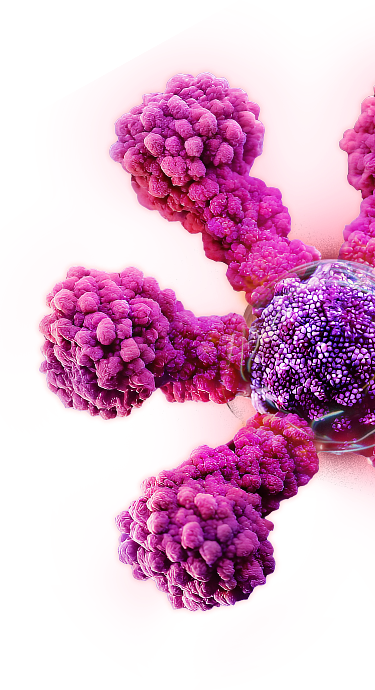

Protein-based Nanoparticles

Our protein-based nanoparticles are made of engineered proteins of the target pathogen to trigger immune system recognition.2